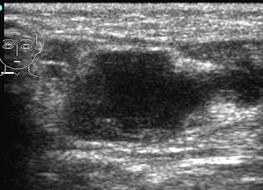

Ультразвуковое изображение острого лимфаденита характеризуется увеличением размеров лимфоузла, неоднородностью структуры, снижением общей эхогенности, исчезновение дифференциации коркового и медуллярного слоя (рис. 5.Б). В режиме допплеровского картирования, при остром лимфадените отмечается усиление кровотока. При этом индекс резистентности (RI) составляет 0,5-0,6.

При гнойном воспалении происходит дальнейшее исчезновение дифференциации слоев лимфоузла. Форма становится шарообразной, истончается капсула. В структуре появляются анэхогенные участки, соответствующие очагам деструкции, которые в дальнейшее сливаются. Картина гнойного лимфаденита представлена на рис. 5.

А Б

Рис. 5. Гнойный лимфаденит (обозначен маркерами)

При прогрессировании заболевания, в дальнейшем происходит разрыв капсулы лимфоузла, гной распространяется за пределы лимфатического узла и происходит развитие аденофлегмоны. Появляется отек, инфильтрация окружающих тканей, обнаруживаются анэхогенные участки рядом с лимфоузлом, соответствующие гнойным затекам (рис. 5.Б.). При хроническом лимфадените происходит утолщение медуллярного слоя, повышается эхогенность структуры. Появляется уплотнение капсулы, происходит появление плотных фиброзных включений.